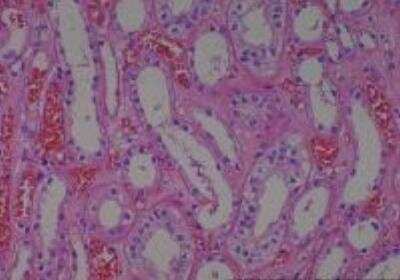

Hematoxylin & Eosin Stain: Human Common Tissue MicroArray (Normal Adjacent) [NBP2-30215] - 01. Stomach